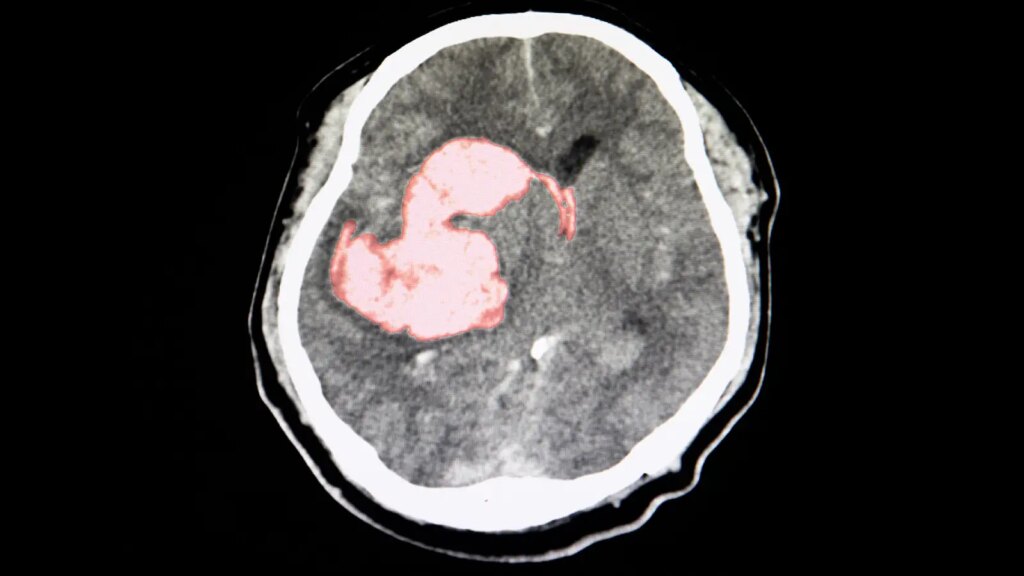

Additional antihypertensive treatment with a three-drug polypill benefitted patients after intracerebral hemorrhage (ICH), the placebo-controlled TRIDENT trial found.

Among ICH survivors already on good background therapy randomized to additional treatment with the GMRx2 polypill — containing telmisartan 20 mg, amlodipine 2.5 mg, and indapamide 1.25 mg — the risk of recurrent stroke was significantly reduced over a median 2.5 years (4.6% vs 7.4% with placebo, HR 0.61, 95% CI 0.41-0.92), according to Craig Anderson, MBBS, PhD, of the George Institute for Global Health, University of New South Wales in Sydney, and colleagues.

The TRIDENT investigators reported that the number of patients who would need to be treated to prevent one stroke was just 35. Of note, recurrent ICH strokes in particular were strongly reduced by polypill therapy (1.8% vs 4.4%, HR 0.40, 95% CI 0.22-0.73).

Anderson and colleagues noted that BP lowering is the only proven treatment to prevent first and recurrent ICH strokes. They cited prior work showing that each 10-mmHg drop in systolic BP was associated with a reduction of approximately 40% in ICH risk.